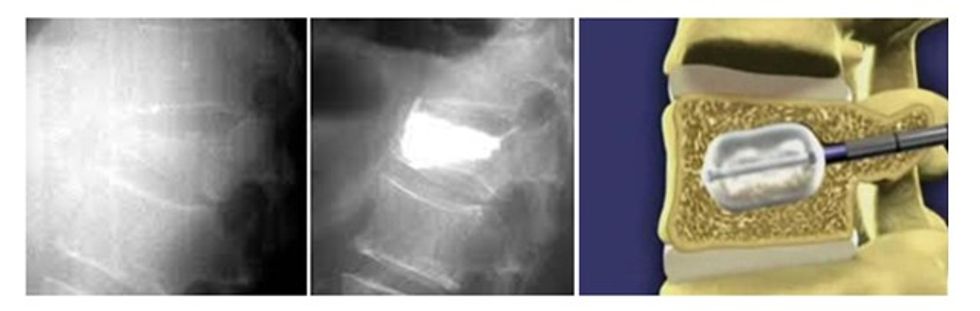

Procedurë tjetër e trajtimit është edhe trajtimi invaziv kirurgjik - aplikimi i cementit në mënyrë të posaçme në trupin e unazës së thyer - Vertebroplastika dhe Kifoplastika.

Procedurat e Kifo dhe vertebroplastikës është procedurë intervente që zgjatë përafërsisht 45 minuta, ku nëpërmjet të gjilpërave specifike arrihet në trupin e unazës së thyer injektohet cementi e që ka për qëllim pengimin e kollabimit të unazës së thyer.

Procedura e tillë mund të aplikohet edhe tek tumoret e ndryshëm metastatik të shtyllës kurrizore e që kanë atakuar trupin e unazave. Pacienti është i lëvizshëm vetëm disa orë pas aplikimit të kësaj procedure. /Telegrafi/